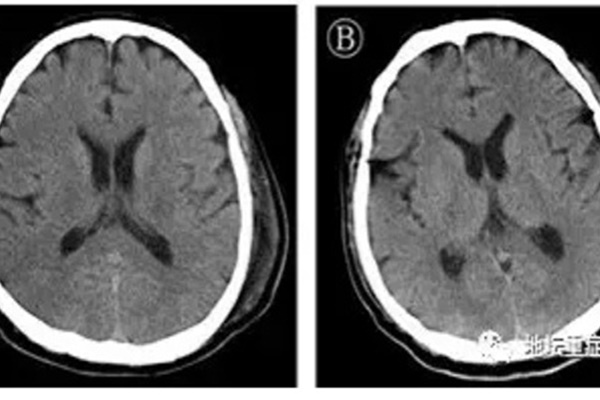

Ảnh chụp não bộ bị virus corona tấn công của bệnh nhân tại Khoa ICU, Bệnh viện Ditan Bắc Kinh. Ảnh: Ecns.

Bệnh nhân là nam giới, 56 tuổi, bị viêm não cùng lúc với viêm phổi. Phác đồ nghiên cứu não của bệnh nhân phát hiện virus corona xâm chiếm hệ thống thần kinh, giống như SARS và MERS đã từng gây ra.

Đây là ca đầu tiên chứng minh chủng mới của virus corona có thể xâm nhập hệ thống thần kinh trung ương của người.

Theo thông tin từ Ecns, bệnh nhân 56 tuổi đã hồi phục và được xuất viện vào ngày 25/2 vừa qua. Người này nhập viện một tháng trước vì suy hô hấp. Các bác sĩ đã giải trình tự gene trên dịch não tủy của bệnh nhân khi nhận thấy các rối loạn thần kinh, co giật sau nhiều ngày điều trị.